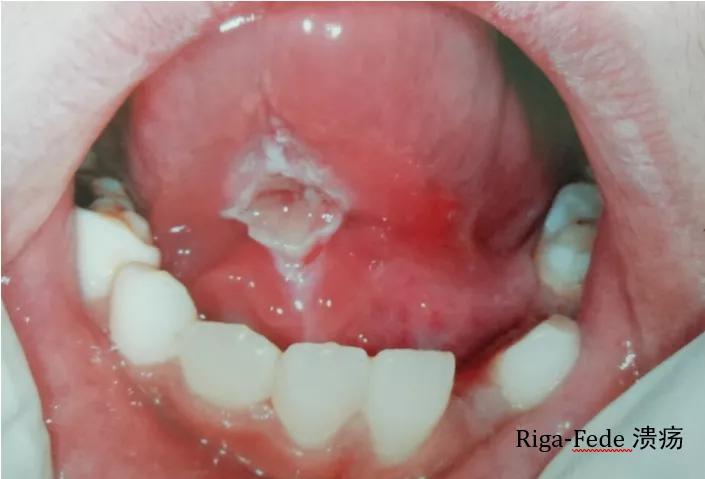

二、李-弗氏溃疡(Riga-Fede溃疡)

有些宝贝刚萌出的下颌前门牙边缘较锐,或者舌系带过短,做吸吮动作时,下前牙不断和舌系带摩擦继而发生舌系带处充血、溃疡。

处理:溃疡局部涂抹消炎促进愈合的药物。对牙齿边缘较锐的应做磨改,减少刺激。对舌系带过短的,应在溃疡愈合后做修整手术。溃疡面较大的可以适当改变喂养方式(比如改用小勺喂食),尽量减少吸吮动作,促进溃疡愈合。